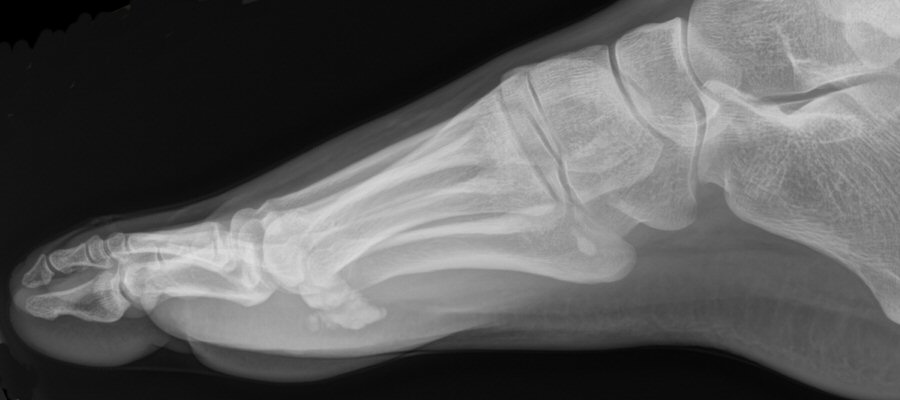

Exempel på bipartit lateralt sesamben